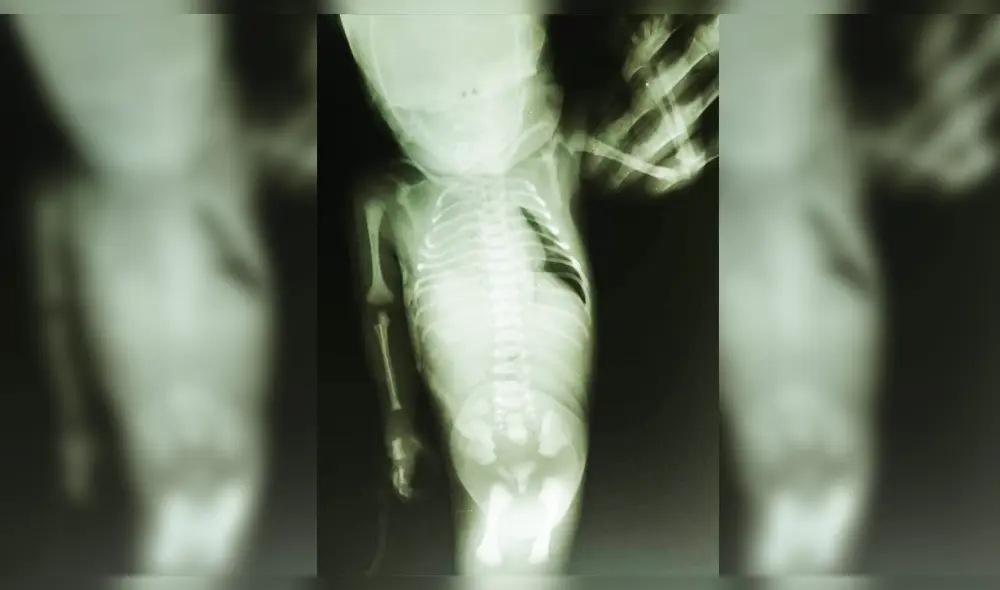

En el hospital de la ciudad de Jaén (región Cajamarca), ha generado sorpresa entre el personal de salud el nacimiento de una “niña sirena”. Esta malformación congénita que es muy poco frecuente, y su principal característica es que el bebé presenta unidas las piernas.

Científicamente recibe el nombre de Sirenomelia. Según el registro, el parto fue por cesárea. Tanto la madre y el padre tendrían entre 18 y 20 años de edad.

Este es el primer bebé de la pareja, quien llegó con esta malformación y otras complicaciones relacionadas con el funcionamiento del riñón y la vejiga.